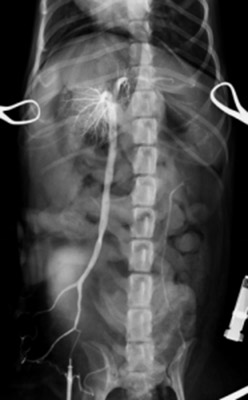

完全結紮後の門脈造影検査:シャント血管の遮断が確認され、血液が完全に肝臓にいっていることが確認されました。

術後は経過良好で、術後5目には退院しました。元気、食欲とも以前よりも良くなり、術後2ヶ月目の総胆汁酸の検査でも正常値に改善したため完治と判断しました。 この病気は先天的な病気ですが気付かれずに進行し、若くして肝硬変になってしまう恐ろしい病気です。予防としては1歳前後の時から健康診断を行い早めに病気を発見してあげることです。